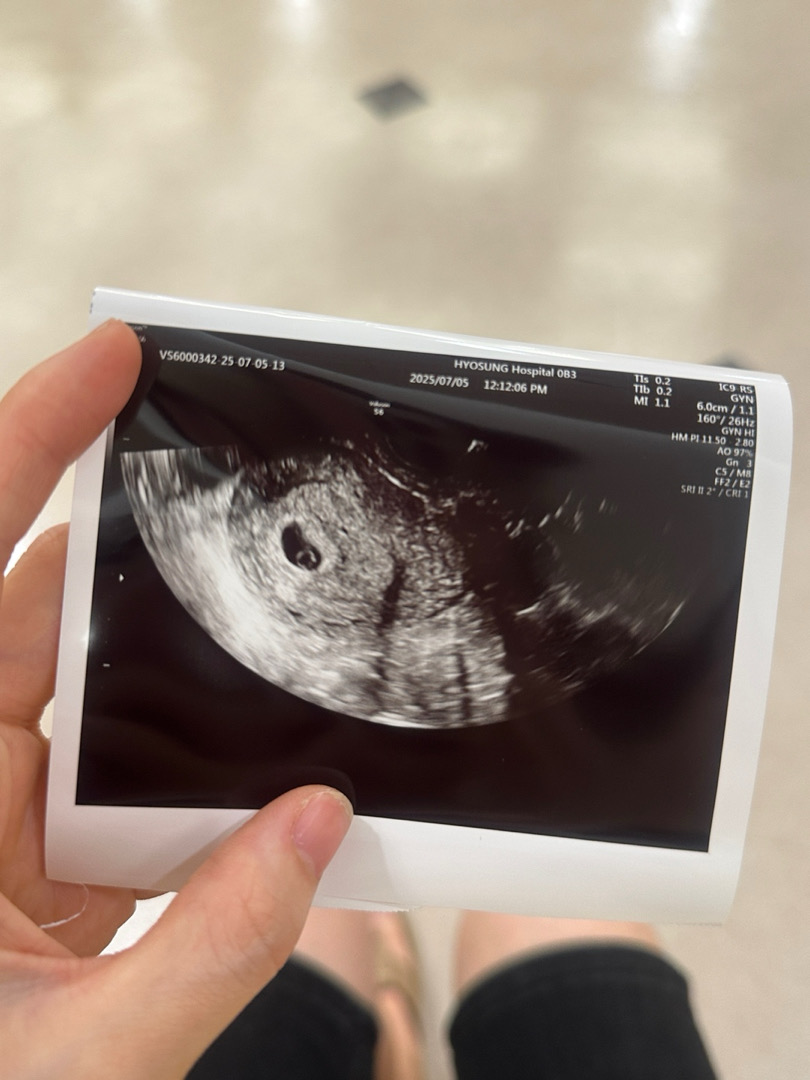

난황크기좀 봐주시면 감사하겟습니다

남편이라 지식이 많이부족합니다.. 막생이 5.23 사진은 7.5일에받은거구 의사선생님 말씀으로는 생리주기가 긴편이라고하시더라구요 내일 병원가는데 와이프가유산경험이있어서 이것저것 다걱정돼서 여쭤봐요 난황크기가 크면 안좋다던데 저는봐도잘모르겟구 정상일까요?!걱정안해두돼려나요 ㅠㅠ